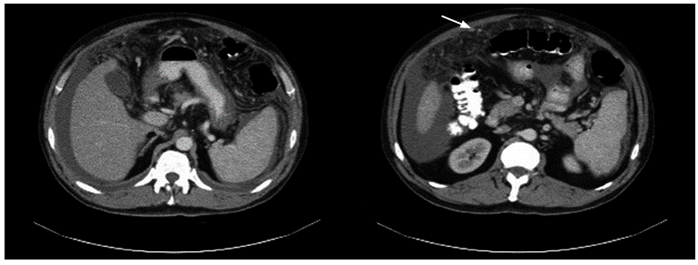

El citoquímico del líquido ascítico mostró un gradiente de albúmina suero-líquido (GASA) de 0,6 compatible con ascitis no hipertensiva; leucocitos de 2400/mm3, 100 % linfocitos, con glucosa en 82,4 mg/dL y coloración de Gram negativa para gérmenes. Se amplió el estudio con niveles de adenosina-desaminasa (ADA) en el líquido peritoneal con un valor de 102 U/L (referencia < 36 U/L) y el citológico mostró linfocitosis y fue negativo para malignidad. Se realizó una tomografía axial computarizada (TAC) de tórax y abdomen con el fin de descartar una neoplasia como diagnóstico diferencial. La TAC de abdomen mostró cambios en la densidad del peritoneo con engrosamiento, múltiples nódulos pequeños en el tercio superior del abdomen que realzaban con el medio de contraste (Figura 1), hígado pequeño y ascitis abundante; y la TAC de tórax mostró escaso derrame pleural bilateral. Se definió realizar una laparoscopia para la toma de biopsias en la que se evidenció un compromiso extenso de todo el peritoneo por micronódulos amarillentos, algunas adherencias interasas, abundante líquido verdoso no purulento en la cavidad, así como hígado de aspecto cirrótico con algunos micronódulos; se tomó biopsia de peritoneo e hígado. El estudio histológico del peritoneo fue compatible con inflamación granulomatosa, con tinción de Ziehl-Neelsen (ZN) negativa (Figura 2), pero con reacción en cadena de la polimerasa (PCR) positiva para Mycobacterium tuberculosis. El enzimoinmunoanálisis de adsorción (ELISA) para VIH fue negativo.

Figura 1 TAC de abdomen contrastada. Hígado pequeño, engrosamiento y múltiples nódulos pequeños en el peritoneo que realzan con el medio de contraste.